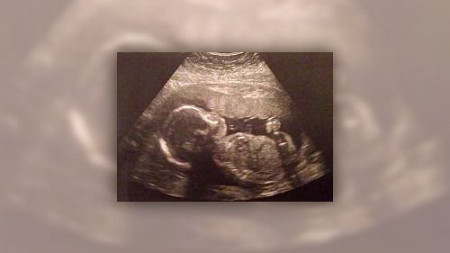

Badania USG w ubiegłym tygodniu wykazały, że dziecko rośnie i rozwija się dobrze.